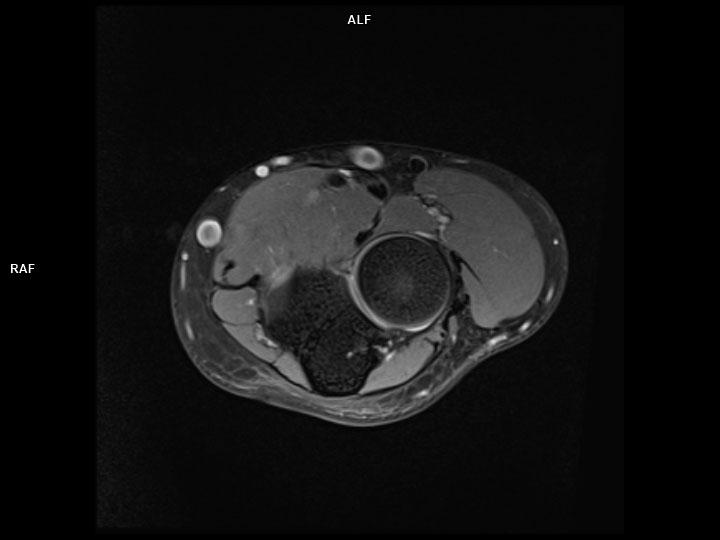

Axial PD FS-MAGNETOM Lumina

Axial PD FS-MAGNETOM Lumina/Coil-UltraFlex 18 Small/Resolution-320/Scan Time-2:26/Aceleration-p2 s2